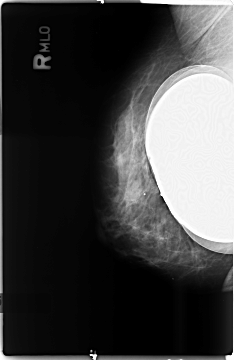

B_3497_1.RIGHT_MLO

DATE_OF_STUDY 5 1 98

PATIENT_AGE 54

DENSITY 3

RIGHT_CC LINES 4648 PIXELS_PER_LINE 3048 BITS_PER_PIXEL 12 RESOLUTION 50 NON_OVERLAY

RIGHT_MLO LINES 4680 PIXELS_PER_LINE 3040 BITS_PER_PIXEL 12 RESOLUTION 50 NON_OVERLAY